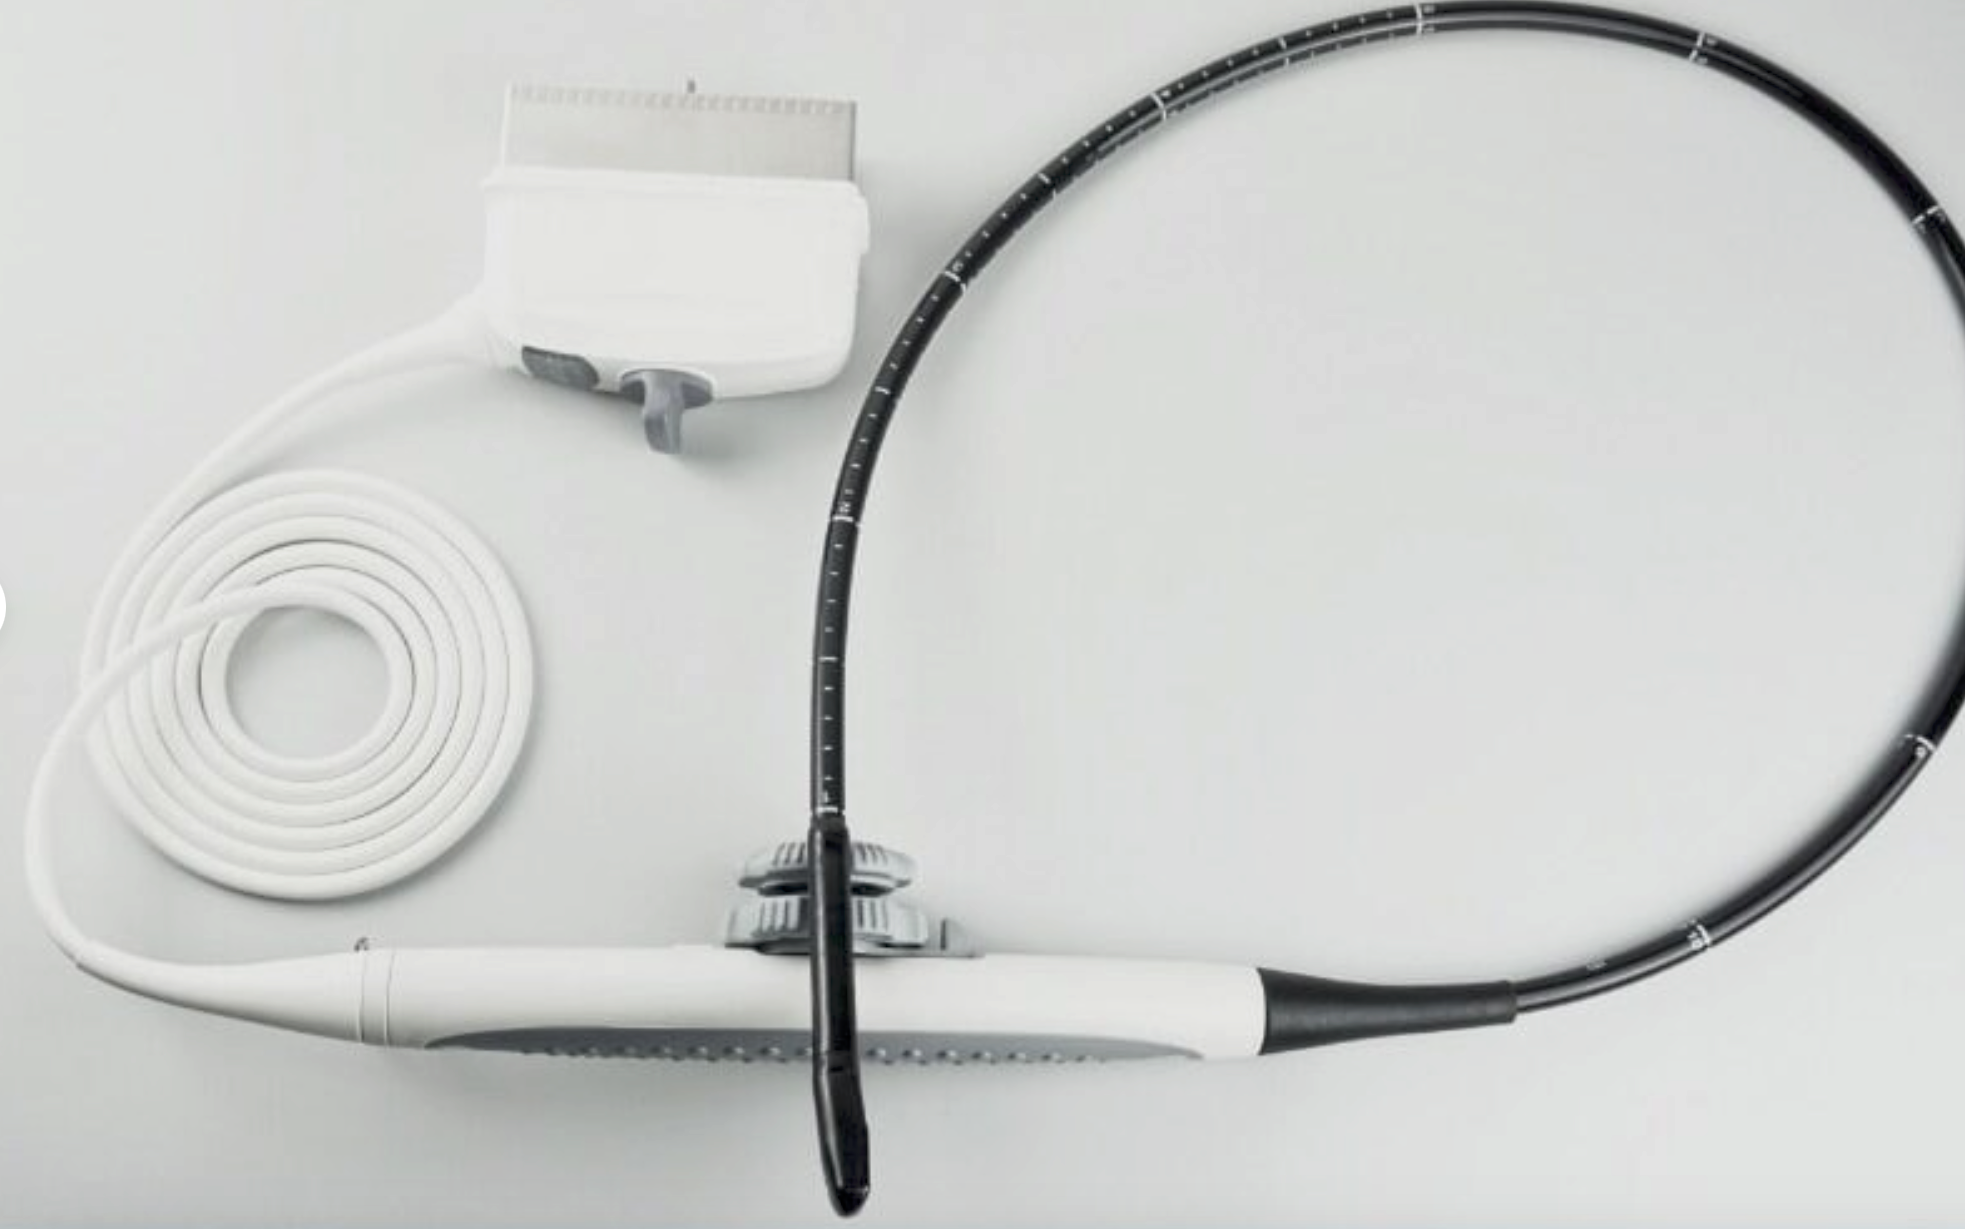

Description

Condition: Used: An item that has been used previously. The item may have some signs of cosmetic wear, but is fully operational and functions as intended. This item may be a floor model or store return that has been used. See the sellerâs listing for full details and description of any imperfections. See all condition definitions- opens in a new window or tab ... Read moreabout the condition

Brand: GE

Model: 4C-RS